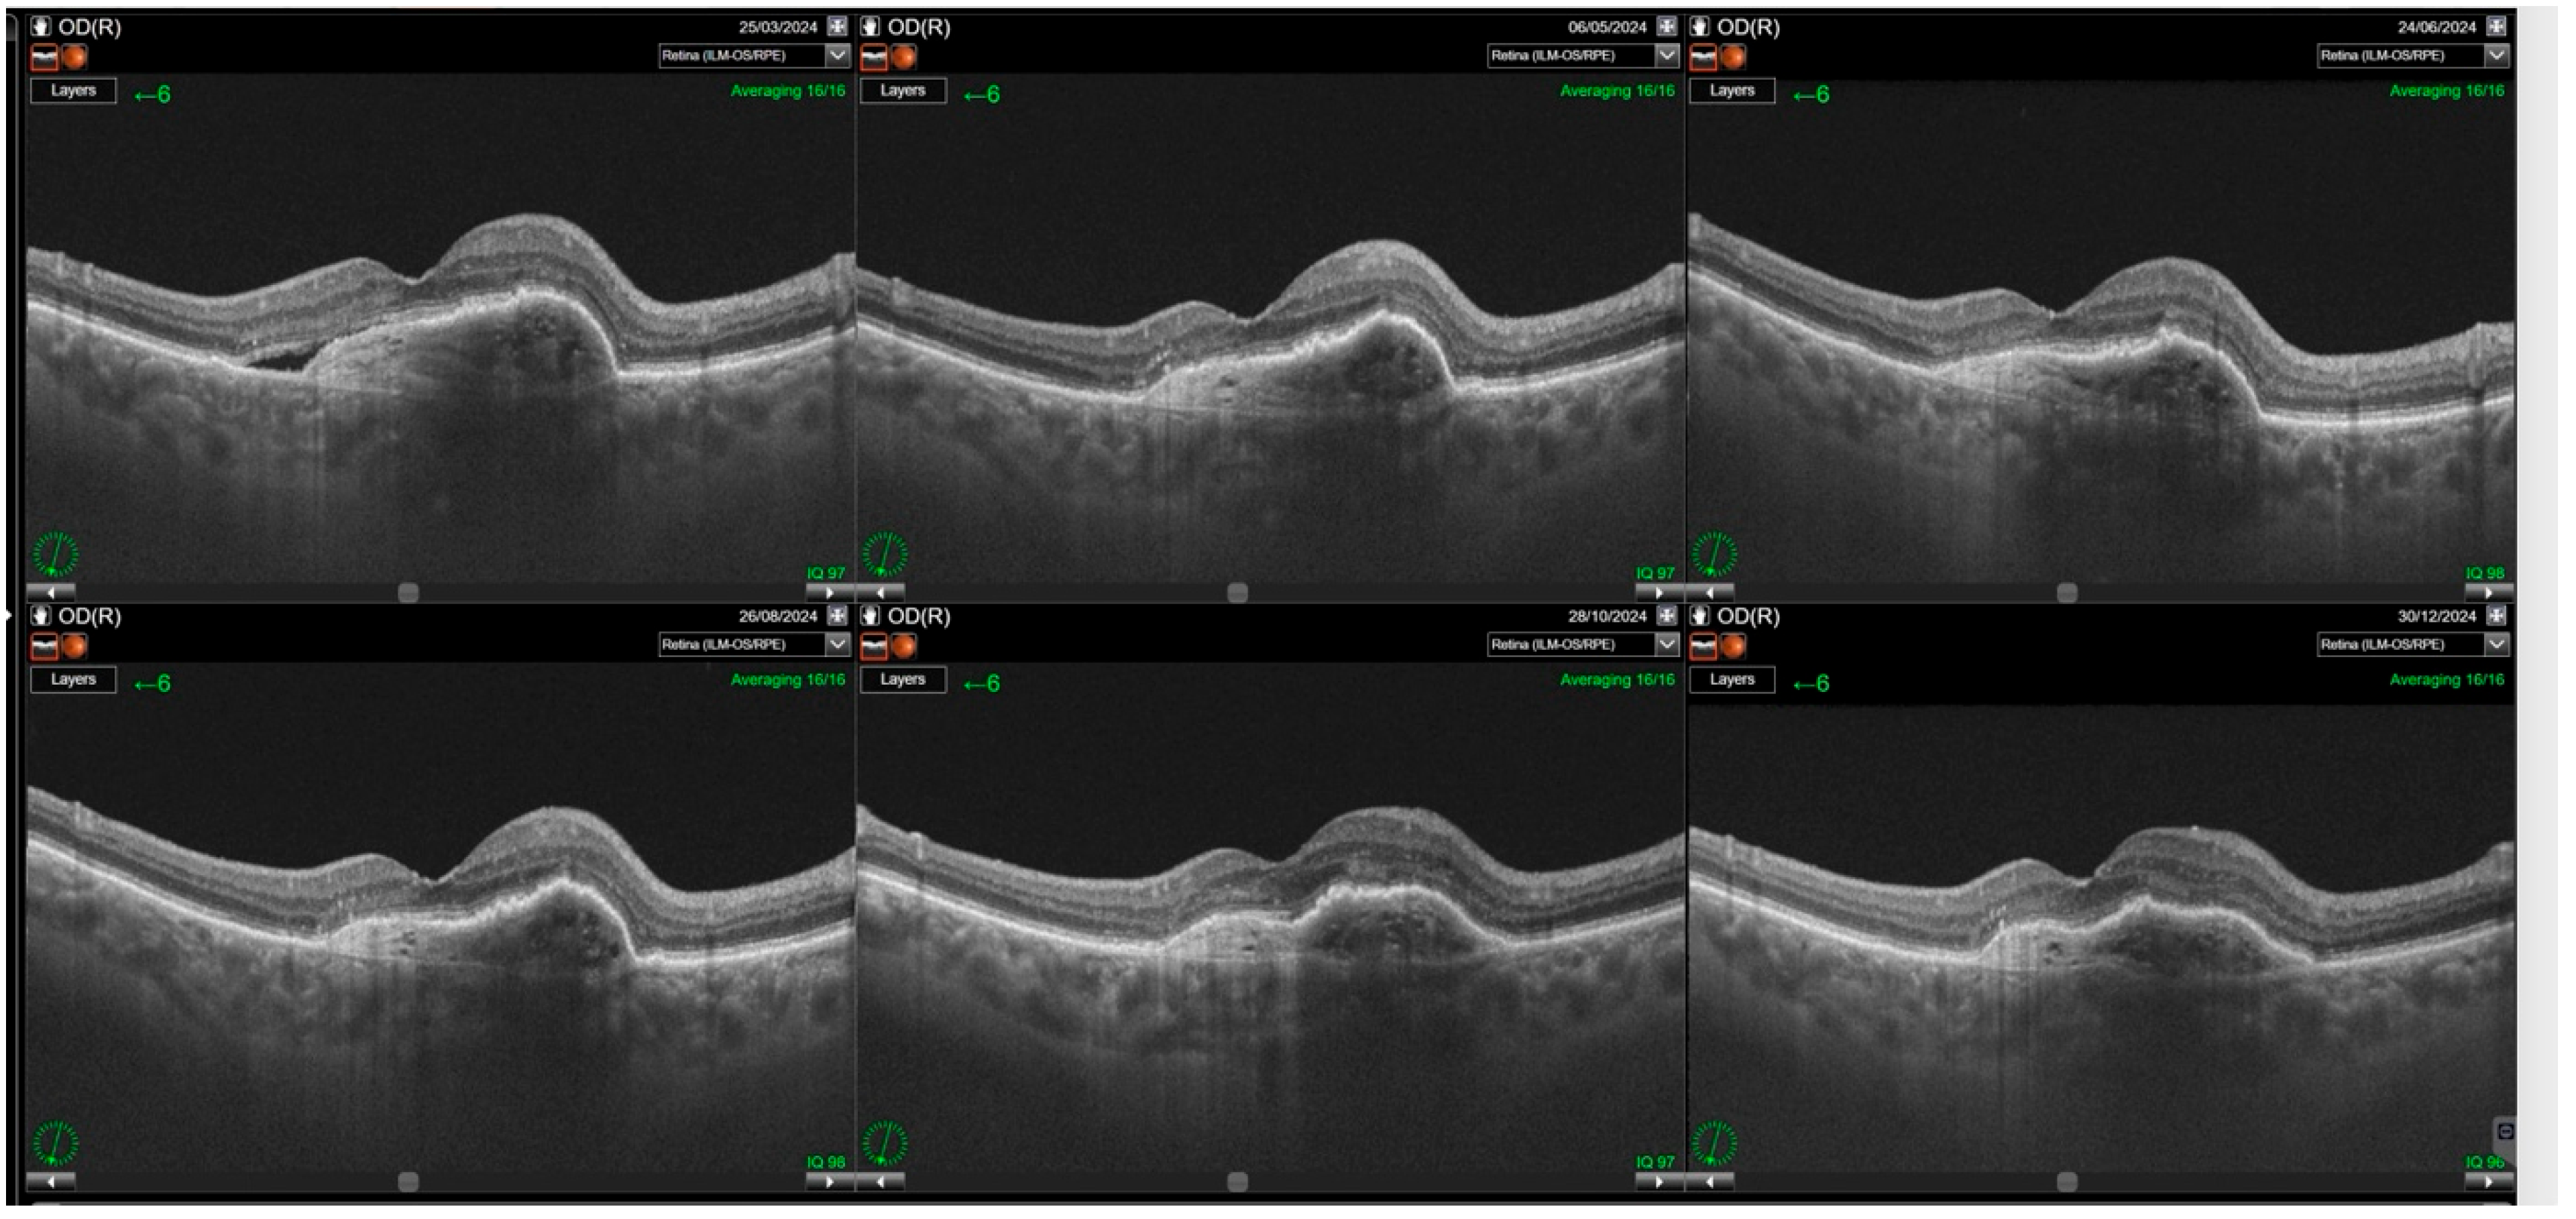

3. Results

3.2. Central Subfoveal Retinal Thickness (CST)